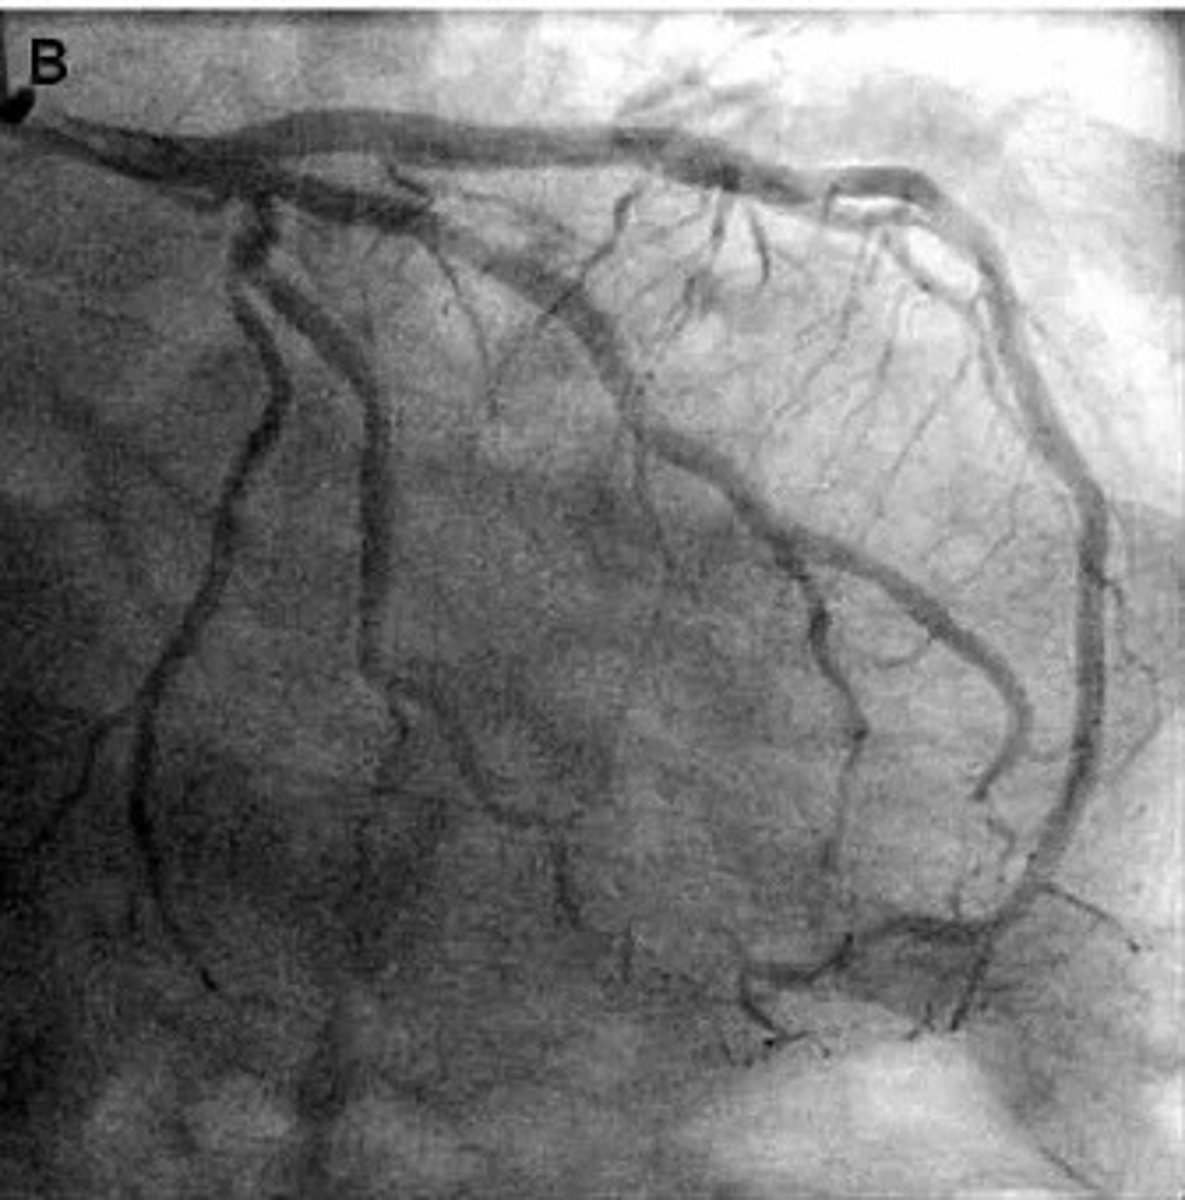

right coronary artery angiogram

what pathology is present?